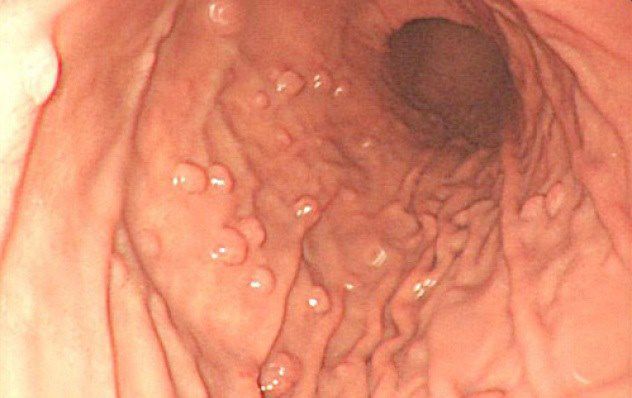

Гиперпластический полип желудка — это образование из эпителиальных клеток, как правило, до 2 см. Однако не исключен их рост до больших размеров. Образование часто имеет ножку, то есть сужение у основания. Сам по себе гиперпластический тип не способен озлокачиваться, но может привести к раку окружающих тканей. Это называется метаплазией эпителия, то есть изменением его клеток.

Формироваться гиперпластические полипы могут практически по всему органу: антральной, кардиальной, фундальной области. Наиболее частое (около 70%) место локализации — поворот желудка, то есть пилорический отдел.

Этот вид образований иногда классифицируют отдельно наравне с аденоматозным и гиперпластическим, но чаще относят к последнему. Гиперплазия — это быстрый рост, формирование, увеличение числа клеток ткани. Поэтому гиперплазиогенные полипы характеризуются стремительным разрастанием. По внешнему виду их сравнивают с цветной капустой. За счет своей гиперспособности к делению клеток такие наросты подвержены риску перерождения в раковую опухоль. Поэтому научная медицина относит гиперплазиогенный полип к предраковому состоянию.